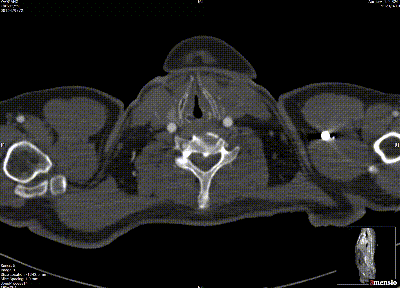

★ Case 1

男性,42岁,胸痛3天;

既往史:高血压,规律服用降压药物;

手术史:10年前外院行主动脉腔内修复+左颈总及左锁骨下烟囱支架植入;

夹层动脉瘤CTA:逆撕A型主动脉夹层,升主动脉及无名动脉见夹层累及,左颈总及左锁骨下动脉烟囱支架。

术前影像